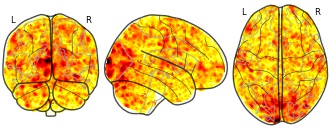

Individual Brain Charting dataset extension, second release of...

EmailClick to copy linkLink copied Cite(2020). Individual Brain Charting dataset extension, second release of high-resolution fMRI data for cognitive mapping: sub-04_ses-12_task-mtt_sn_dir-pa_run-01_sn_northside_event [Dataset]. http://identifiers.org/neurovault.image:364810niftiAvailable download formatsUnique identifierhttps://identifiers.org/neurovault.image:364810Dataset updatedFeb 14, 2020License

Cite(2020). Individual Brain Charting dataset extension, second release of high-resolution fMRI data for cognitive mapping: sub-04_ses-12_task-mtt_sn_dir-pa_run-01_sn_northside_event [Dataset]. http://identifiers.org/neurovault.image:364810niftiAvailable download formatsUnique identifierhttps://identifiers.org/neurovault.image:364810Dataset updatedFeb 14, 2020LicenseCC0 1.0 Universal Public Domain Dedicationhttps://creativecommons.org/publicdomain/zero/1.0/

License information was derived automaticallyDescriptionCollection description

The individual Brain Charting (IBC) Project is using high resolution fMRI to map 13 subjects that undergo a large number of tasks: the HCP tasks, the so-called ARCHI tasks, a specific language task, video watching, low-level visual stimulation etc. The native resolution of the data is 1.5mm isotropic. Their main value lies in the large number of contrasts probed, the level of detail and the high SNR per subject. This dataset is meant to provide the basis of a functional brain atlas. We upload here smoothed individual SPMs. The uploaded maps comprise session-specific and fixed effects across maps acquired with AP and PA phase encoding directions.

Note that Neurovault collection #4438 is a subset of that one. In the present collections, some details have been fixed, including mroe accurate and unique file naming.

Subject species

homo sapiens

Modality

fMRI-BOLD

Analysis level

single-subject

Cognitive paradigm (task)

Mental time travel task

Map type

Z